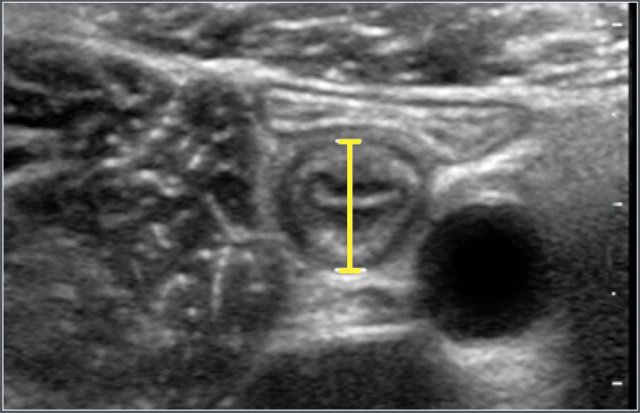

Ultrasonographic anteroposterior measurement of the appendix.

Ultrasonographic measurement of wall thickness of terminal ileum in a 12-year-old boy with cystic fibrosis.